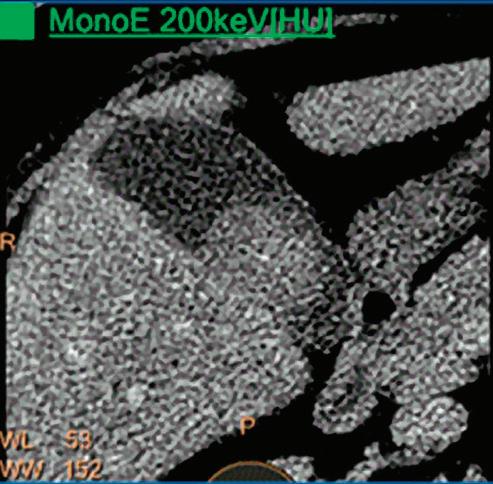

CT breath-hold results in a poor enhancement of the pulmonary arteries on the displays from left to right: monoenergetic 70 keV, monoenergetic 55 keV, monoenergetic 40 keV, and Z effective map showing a perfusion deficit of the lung parenchyma (white arrow). When decreasing the energy, the iodine attenuation is progressively boosted and reveals the presence of a thrombus (colored arrows) in a sub-segmental pulmonary artery corresponding to the territory of the perfusion deficit. (c) Monoenergetic 200 keV reduces beam hardening from dense contrast medium compared to conventional CT images.

Once the pair (αp, αc) is calculated for every voxel, and since fp(E) and fc(E) are known functions of energy, one may synthesize monochromatic images at different energies. These images can be used for routine diagnosis similar to conventional images. With a single scan at 120 kVp (or 140 kVp for obese patients), a dual-layer spectral CT acquisition allows the reconstruction of virtual monochromatic images from 40 keV up to 200 keV, in increments of 1 keV. The minimum of 40 keV was chosen in order to stay above the k-edge of the most common materials including iodine (iodine k-edge = 33 keV). If the scan is performed at 120 kVp, the conventional CT images of a typical-size patient will display an attenuation corresponding to the average of the X-ray spectrum (˜70 keV in a body scan) but with beam hardening artifacts from dense structures (like bones) which are due to the polychromatic nature of the X-ray beam. Since the photoelectric effect is dominant at lower keV, and is relatively high for high Z materials, low keV imaging (below 70 keV for body) can be used to enhance the absorption of high Z material such as iodine (Z=53), compared to the conventional CT images.15,16 This can be of particular interest to enhance the iodine uptake for patients with renal dysfunction, where the total injected volume of iodinated contrast medium is very limited. This attenuation boost can also be very useful in the case of a missed injection (Figure 2a and b). Compton scattering on the other hand is dominant at higher keVs and does not exhibit a strong relationship with Z. High keV imaging will then be of particular interest to minimize the absorption of high Z materials and minimize all types of associated artifacts (metal beam hardening from metal implants, beam hardening from dense contrast medium, blooming of stents or calcium, etc.) (Figure 2c).17,18,19